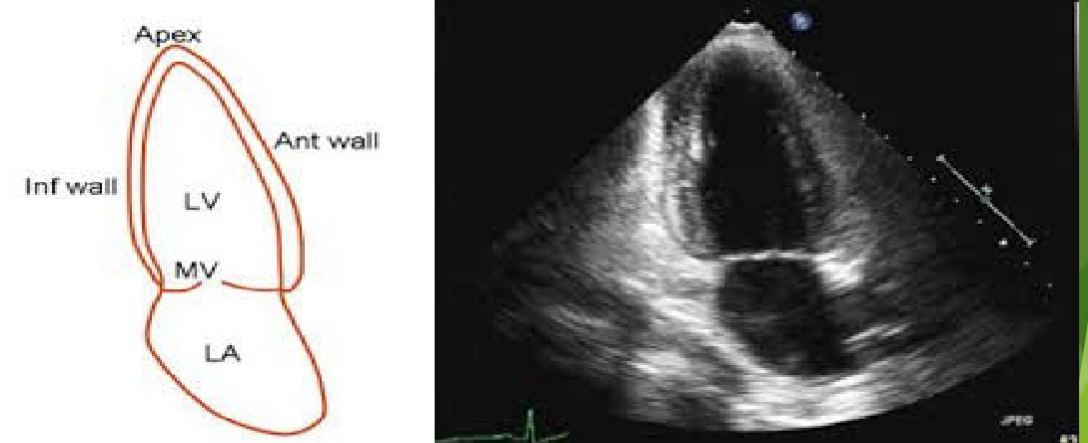

<p>What view is this?</p>

What view is this?

Apical 3 Chamber